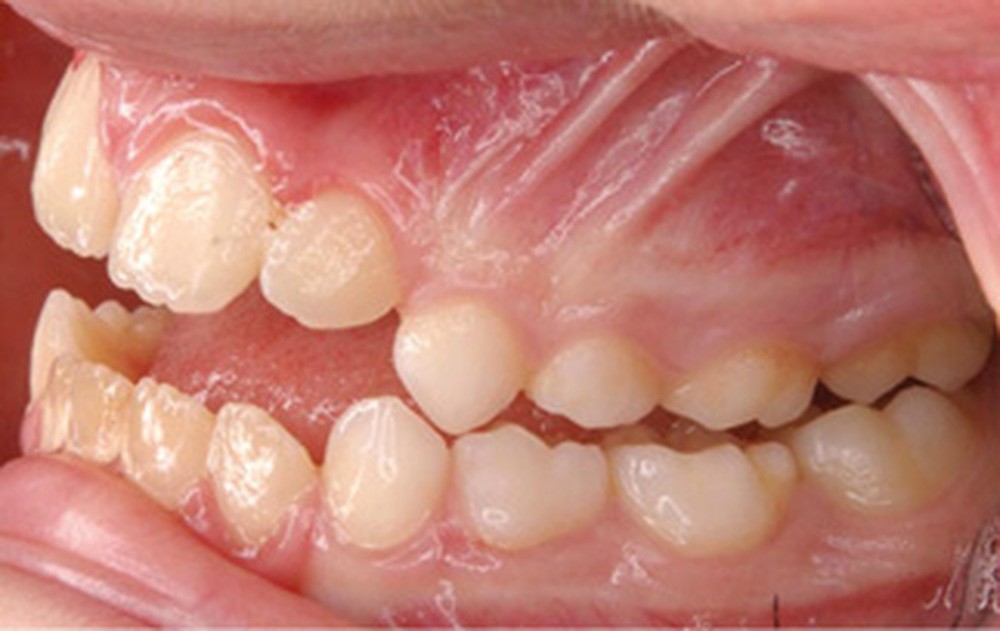

Quelques années plus tard, au moment de démarrer sa prise en charge orthodontique, la patiente présentait à nouveau une béance antérieure, un décalage des milieux incisifs de 2 mm et le problème transversal avait récidivé. Lors de l’examen clinique, elle présentait un inversé d’occlusion bilatéral postérieur et une ventilation buccale exclusive. À la suite du refus de réaliser l’amygdalectomie de façon précoce, elle ronflait toujours et sa déglutition ne s’était pas modifiée malgré des séances d’orthophonie (fig. 7 à 15).